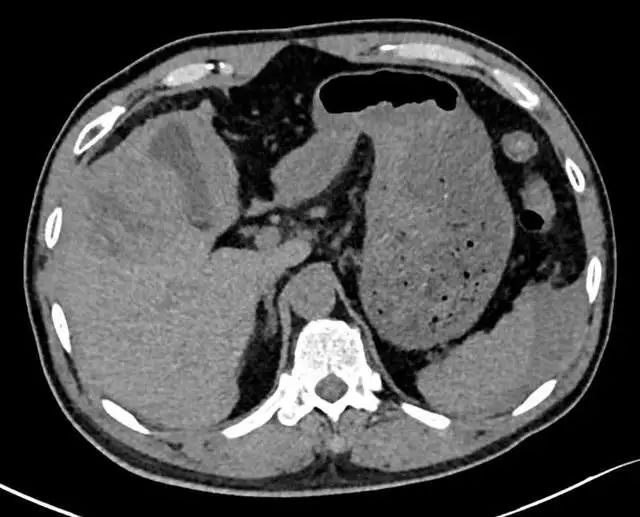

120接到一位口吐鲜血的患者,看到患者时大家都感到很熟悉,记得上一次入院是因为发现了肝癌,这次却再一次发病入院。

患者男38岁,之前因为腹痛、乏力入院发现是肝癌晚期,患者早在10年前就发现自己是乙肝病毒携带者,由于对乙肝的不了解,再加上身边有同样的乙肝患者支招,因此即使发现乙肝也没有再做任何治疗和检查。

肝癌患者为什么会出现吐血?

当肝癌伴有肝硬化时,会引起静脉曲张,包括食管胃底静脉丛、直肠静脉丛、腹膜后静脉丛、腹壁静脉丛等等。胃底静脉曲张可导致血管凸出于胃壁表面。如果吃的食物过于粗糙或胃酸分泌增多时,可引起消化道出血,后果严重的还会导致死亡;

肝癌晚期门静脉出现癌栓,门脉压力短时间内迅速升高,导致消化道大出血,因此会出现呕血。